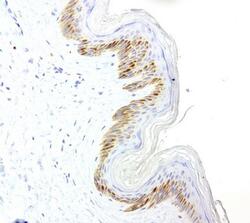

- Submitted by

- Invitrogen Antibodies (provider)

- Main image

- Experimental details

- Immunohistochemical staining of paraffin-embedded human skin using anti-VSNL1 clone UMAB115 mouse monoclonal antibody (UM800034) at 1:200 with Polink2 Broad HRP DAB detection kit; heat-induced epitope retrieval with GBI Citrate pH6.0 HIER buffer using pre